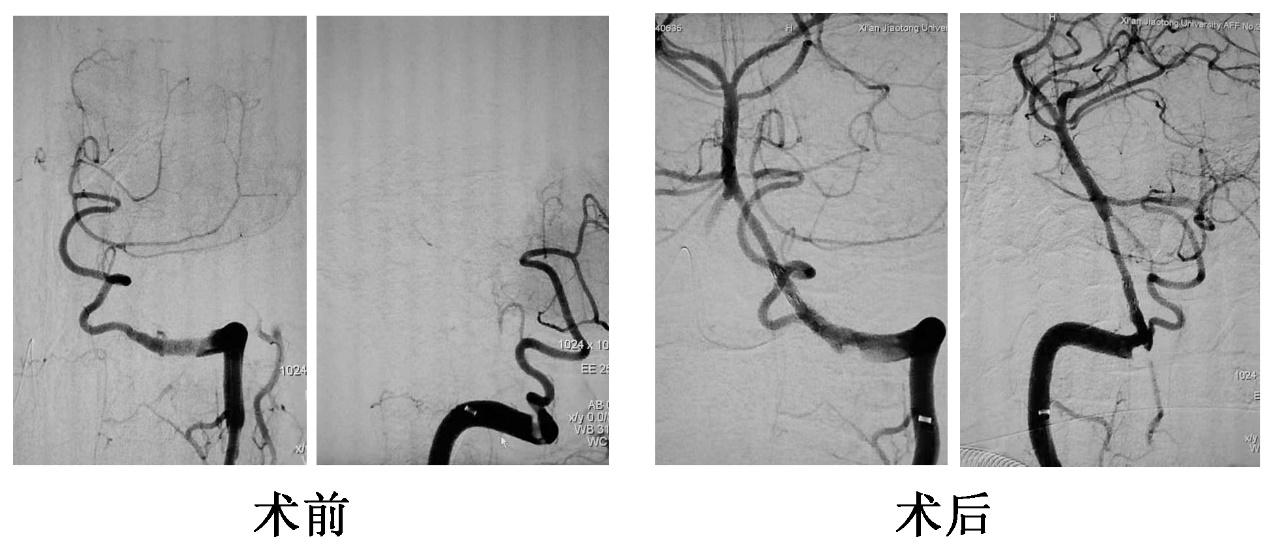

神经内科急诊介入团队王虎清教授、樊洪医师、蒋鹏鹏护士立即响应,30分钟内到达神经介入治疗室,王虎清教授迅速与家属沟通:目前后循环闭塞脑梗死诊断明确,病情危重,极有可能出现意识障碍进行性加重,出现昏迷及四肢瘫痪等情况。在家属知情同意下立即对患者进行了脑血管造影,造影显示双侧椎动脉闭塞,基底动脉远端虽有前循环逆向代偿,但基底动脉近端未见有效代偿,且左侧椎动脉V4段闭塞近端可见局部充盈缺损,大负荷血栓可能,情况危急。急诊麻醉医师迅速到位,进行全麻。针对患者病变特点,制定了血栓抽吸结合球囊扩张联合支架植入的综合开通预案。术中,连续两次抽吸未能将血栓抽出,结合患者症状变化特点及血管病变特征,考虑可能为附壁血栓,迅速调整治疗方案,予以球囊扩张联合支架植入,并覆盖血栓,最终在神经内科急诊介入团队的努力下,基底动脉前向血流恢复正常。术后立即进入NICU单元,给予持续镇静镇痛治疗。术后3小时复查颅脑CT未见明显异常,拔管后患者意识清醒,可按指令活动四肢。目前患者已脱离病危状态,康复科正在进行床旁康复训练,促进神经功能恢复。

术前术后椎-基底动脉对比,术后患者椎-基底脉动脉再通